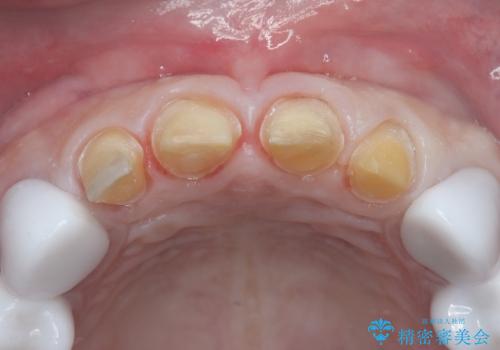

- 治療計画

治療では、まず古いクラウンを慎重に取り外し、歯肉の状態を整えました。その後、精密な型取りから患者様一人ひとりに合わせたオーダーメイドのオールセラミッククラウンを作製。金属を一切使用しないため、歯肉の変色を防ぎ、天然歯のような透明感と美しさを再現します。新しいクラウンは、歯肉のラインに合わせてぴったりと適合するよう調整し、見た目の違和感を解消。長年の悩みが解決し、自然で美しい口元と笑顔を取り戻していただけました。